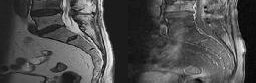

Figures 1 and 2 show sagittal and axial MRI from an 83-year-old woman with an ataxic gait, loss of dexterity, and intermittent loss of bowel and bladder control. The symptoms have been getting progressively worse over the past several weeks.

What disease process is most likely the cause of the patient’s symptoms?

4. Pigmented villonodular synovitis Discussion: B

The patient has a pannus at the C1-2 articulation that is compressing the spinal cord and causing myelopathy symptoms. The development of a pannus at this location has been associated with rheumatoid arthritis. Steinberger and associates showed increased morbidity and mortality when using an anterior approach and the surgery took longer than 4 hours. Chieng and associates showed better outcomes and lower complications rates using a posterior approach.

Question 12 of 100

CLINICAL SITUATION

When discussing anterior versus posterior surgical techniques, you counsel this patient that

Discussion: A